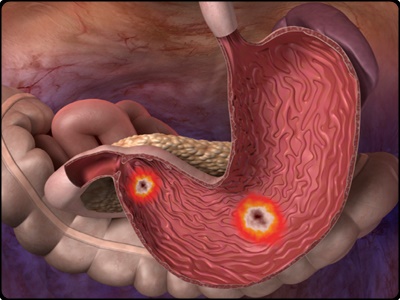

위산 분비가 감소하면서 동시에 소화기능이 저하되면 위 점막에 있는 세포가 변형을 일으키게 됩니다. 그리고 소화기능 저하라는 초기증상으로 나타나게 됩니다. 이는 위암 발생 위험도가 6배나 높습니다. 그리고 위축성 위염이 된 위는 정상인의 위로 회복이 불가능합니다.

하지만 위암으로 발전하지 않게 하도록 연속적인 관리가 필요합니다. 때문에 정기적으로 꾸준히 위내시경 검사를 하는 것이 중요합니다. 때문에 위암을 미리 예방하기 위해서는 나트륨 과다섭취를 피하는 것이 좋습니다. 가능하면 위벽을 자극하지 않도록 해야만 합니다. 위가 자극을 받게되면 위궤양을 일으키고 암세포를 생성하게 됩니다.